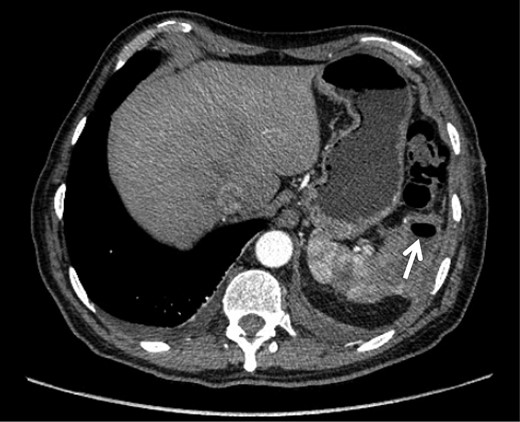

On admission, physical examination revealed normal vital signs and decreased breath sounds over the right pulmonary base as well as diffuse abdominal tenderness that was worse over the left hypochondrium. Blood culture samples as well as a complete blood count that revealed a normal hemoglobin and white cell count were taken. A CT scan confirmed the previously mentioned findings (Fig. 1). The patient was started on the same i.v. antibiotics he had been receiving (meropenem) and then taken to the operating room (OR) for video-assisted thoracoscopic lung decortication/pleurectomy. General surgery was then asked to assess the splenic abscess and, in consultation with interventional radiology, chose to treat conservatively. Two days later, the antibiotic regimen was simplified to i.v. ertapenem. After 4 days of this management, a new CT showed that the abscess had grown in size and had gas within it (Fig. 2). The decision was made to take the patient to the OR for a laparoscopic splenectomy.

CT scan taken 5 days after admission demonstrating an increase in the size of the splenic abscess as well as the presence of gas within its walls (arrow).